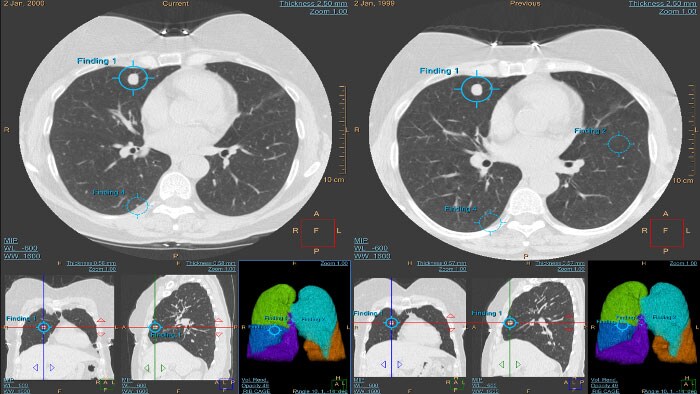

CT Lung Nodule Assessment (LNA)

Pacote de imagiologia avançada para a segmentação e quantificação de nódulos pulmonares. Suporte para a deteção, diagnóstico e acompanhamento dos nódulos pulmonares, mesmo em exames torácicos por TC de baixa dose.